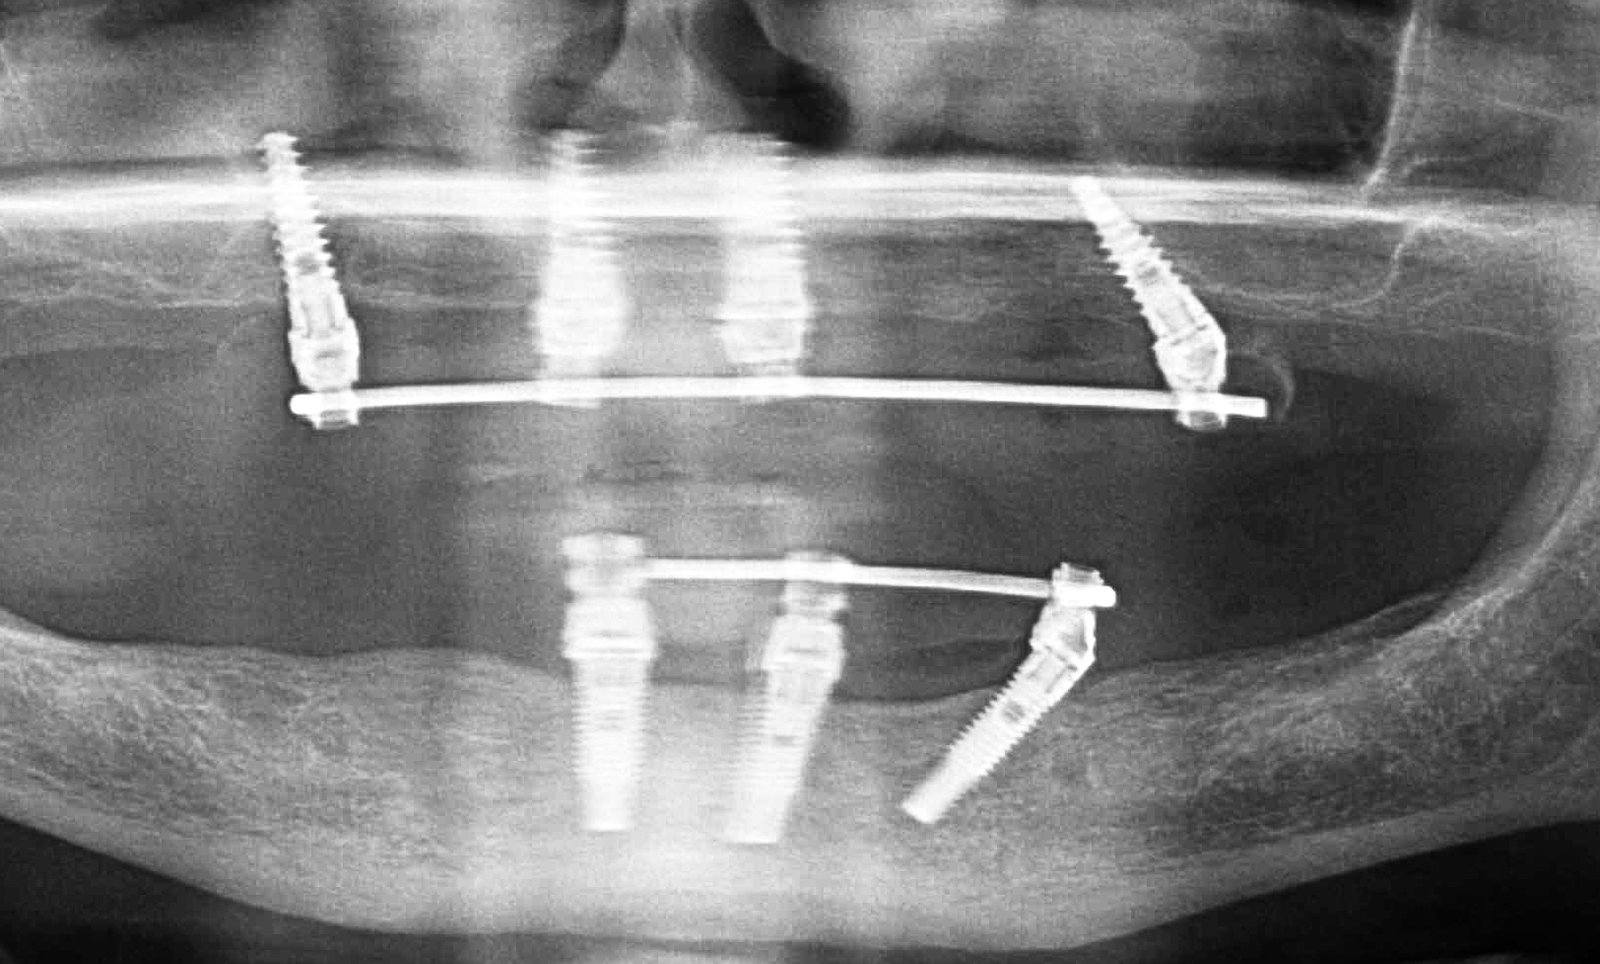

Estimados compañeros...necesito ayuda...cómo lo veis? Alguna idea? Según el paciente puestos en IDental y me trae esta Orto... Marca...compatibilidades... Gracias!